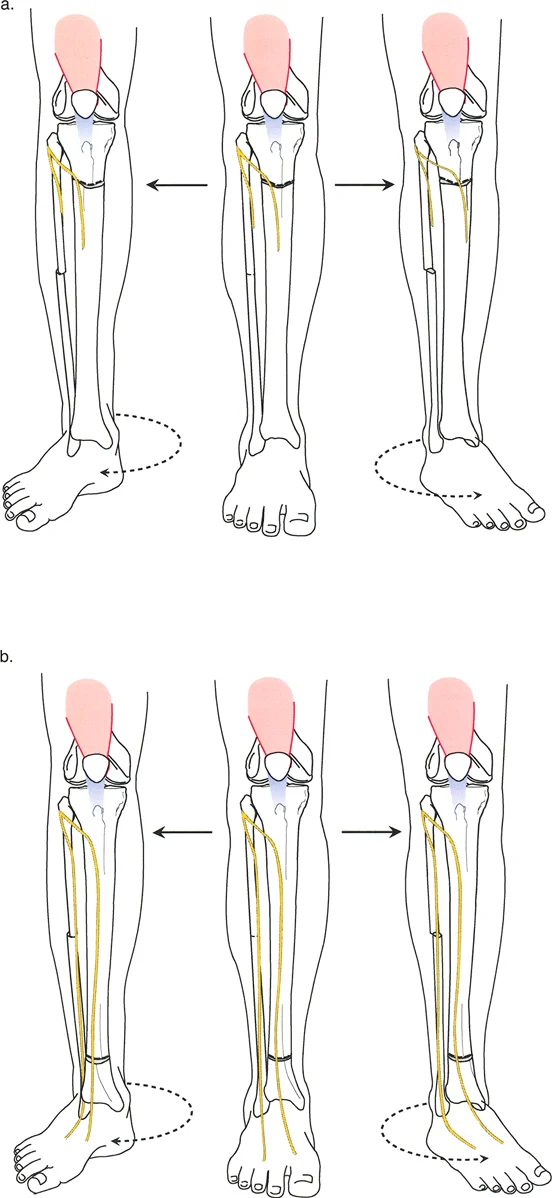

* الدوران الظنبوبي (Tibial Torsion): التواء في عظم قصبة الساق، يمكن أن يكون داخلياً أو خارجياً، ويؤثر على اتجاه القدم.

تحليل دوران قصبة الساق (Tibial Torsion Analysis)

يتبع تحليل دوران قصبة الساق (Tibial Torsion) منطقاً مشابهاً ولكنه يعتمد على معالم تشريحية مختلفة (الكاحلين). يحدد هذا التحليل مدى التواء عظم قصبة الساق.

1. بروتوكول التصوير: يتم الحصول على صورتين بالأشعة السينية (AP و Lateral) للكاحل مع توجيه صابونة الركبة للأمام.

2. القياس: يتم قياس المسافة العرضية بين الكاحل الإنسي والوحشي على كلتا الصورتين.

3. الرسم البياني: يتم رسم هذه القيم على رسم بياني للمستوى المائل لتحديد اتجاه مستوى الكاحلين.

4. المقارنة: تُقارن زاوية الدوران المحسوبة بالجانب الآخر السليم أو بالنطاق الفسيولوجي الطبيعي (عادة 15° ± 5° من الدوران الخارجي).